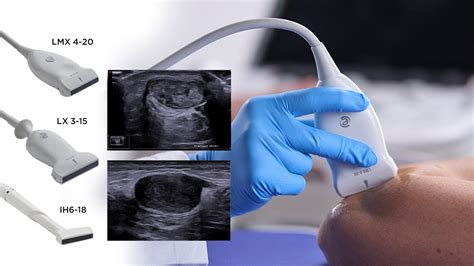

Nuhalna svetlina je neinvazivna ultrazvočna preiskava, ki se izvaja med 11. in 14. tednom nosečnosti. Njen glavni namen je oceniti tveganje za kromosomopatije, kot sta Downov sindrom, Edwards in Patau sindrom. Meritev debeline tekočine v zatilju ploda, skupaj z drugimi parametri, kot sta srčna frekvenca ploda in prisotnost nosne kosti, omogoča izračun verjetnosti za določene genetske nepravilnosti.

Kljub temu, da je nuhalna svetlina pomembno diagnostično orodje, je pomembno razumeti, da gre za presejalni test, ne za dokončno diagnozo. Če test pokaže povečano tveganje, se običajno predlagajo nadaljnje, bolj invazivne preiskave, kot sta amniocenteza ali odvzem horionskih resic (CVS), ki lahko zanesljivo potrdijo ali izključijo prisotnost kromosomskih nepravilnosti.

Te informacije, skupaj s priporočili izkušenih kolegov, lahko bodočim staršem pomagajo pri izbiri najprimernejšega strokovnjaka za svoje potrebe. Samoplačniški ultrazvočni pregledi v nosečnosti, kot so nuhalna svetlina, morfologija ploda, preverjanje plodove rasti in ocena stanja pri tvegani nosečnosti, merjenje pretokov skozi različne žile ploda in popkovino, merjenje materničnega vratu ter posveti v nosečnosti, na primer o porodu pri medenični vstavi ali dvojčkih, so na voljo preko zasebnih ambulant, kjer je pogosto mogoče dobiti tudi več informacij in bolj personaliziran pristop.